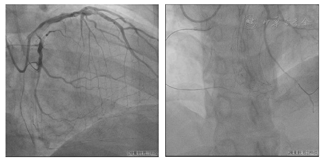

患者无法提供外院冠状动脉造影影像,于2022年6月17日我院行冠状动脉造影提示右冠状动脉中远段完全闭塞,回旋支重度狭窄,前降支轻度狭窄(图3)。

患者存在劳力性胸闷、气促症状,心脏超声未提示下壁节段性室壁运动分析异常,左心室明显扩大,LVEF减低,无室壁瘤,右冠状动脉中远段CTO,J-CTO评分4(钝头,造影未见钙化,>20 mm,成角>45°,有既往LAD-PCI失败史)。考虑右冠状动脉PCI难度大,需要考虑逆向介入可能,决定择期行RCA-CTO介入治疗,造影同期处理回旋支病变(图4)。